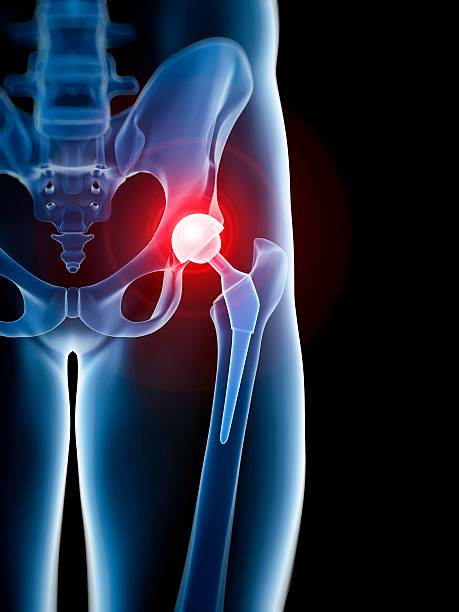

La PTH est l'une des interventions chirurgicales les plus efficaces et les plus étudiées en orthopédie. Elle restaure une articulation indolore avec une durée de vie implantaire de 15 à 20 ans en moyenne.

Le choix de la voie d'abord (postérieure, antérieure de Hueter, ou de Röttinger) et du type d'implant (cimenté, non cimenté, hybride) est individualisé selon l'anatomie, l'âge et l'activité du patient.

Le protocole de Récupération Améliorée Après Chirurgie (RAAC) permet une mise en charge dès le jour de la chirurgie et un retour à domicile accéléré.